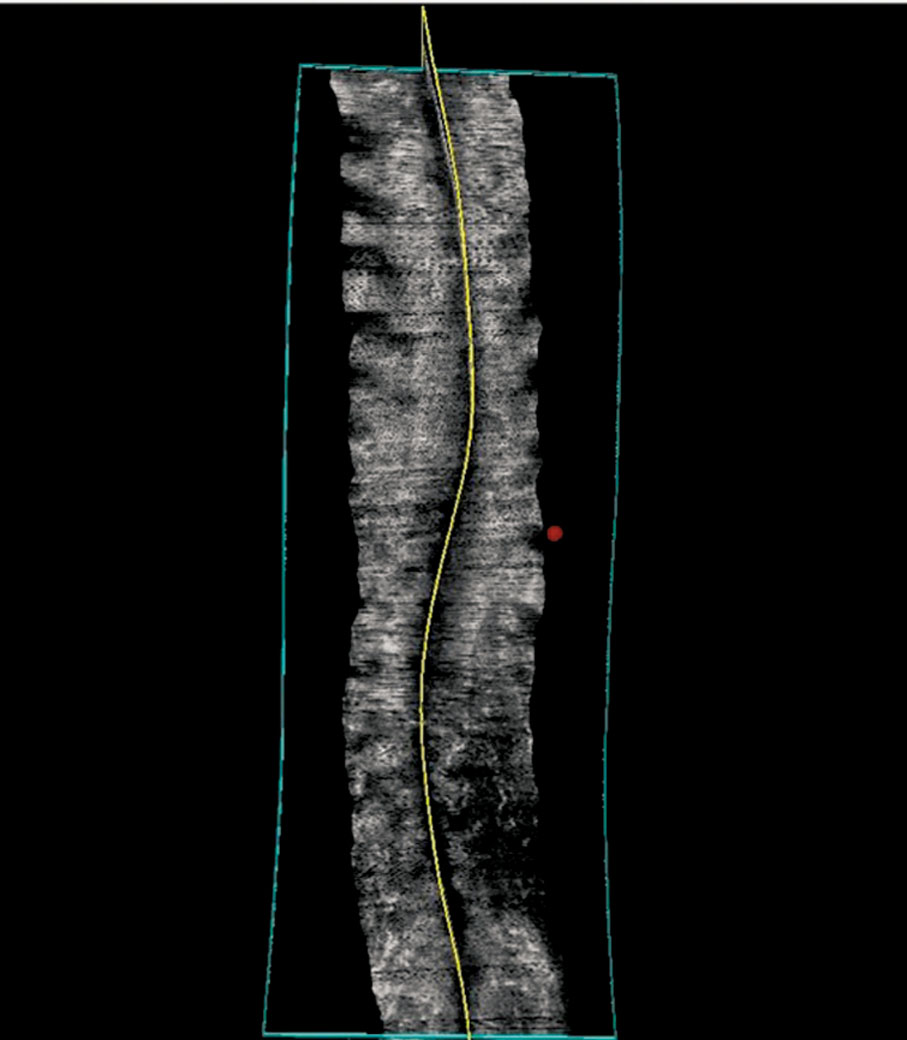

鄭永平帶領研究團隊研發「Scolioscan®醫療系統」,應用三維超聲波成像技術,產生類似放射攝影的脊柱圖像。2012年成立公司中慧醫學,今年4月完成近4,000萬港元的Pre-A輪融資,投資方包括復星醫藥、AEF大灣區創業基金、理大創業投資基金及部分產業投資者。中慧醫學至今獲得逾一億港元的資金。

「問題在於超聲波一般只看到軟組織,例如看BB、心、肌肉等,我們其中一個創新點正正在於此,因為過去從來無人想過,超聲波可以對骨頭形成圖像,可以說是將不可能變成可能。」鄭永平解釋,超聲波可以穿透軟組織,從而可作掃描,「但一打到骨頭,就會經表面反射,根本傳不到骨頭裏面。」